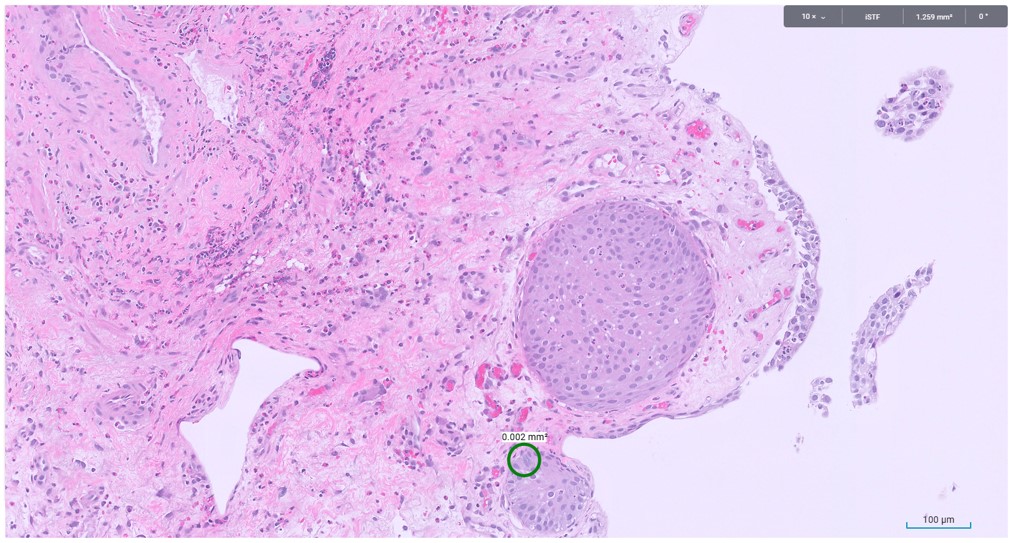

Microscopic image possibly detecting cancerous areas in human tissue

What is the most likely diagnosis?

1. Radiation cystitis

2. Cystitis cystica

3. Invasive urothelial carcinoma

4. carcinoma in situ

Radiation cystitis